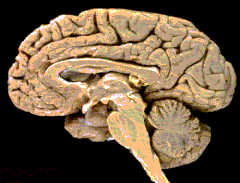

If we look into the skull at the front of the head, we will find the prefontal area of the cerebrum. What does physiology tell us about the function of this area? A book entitled, Essentials of Anatomy & Physiology, says about this area: The motivation and the foresight to plan and initiate movements occur in the anterior portion of the frontal lobes, the prefontal area. This is a region of the association cortex... The book also says: In relation to its involvement in motivation, the prefrontal area is also thought to be the functional center for aggression...

So, this area of the cerebrum is responsible for planning, motivating, and initiating good and sinful behavior, and is responsible for telling lies and speaking the truth. Thus, it is proper to describe the front of the head as lying and sinful when someone lies or commits a sin, as the Qur’an said: ...a lying, sinful naasiyyah (front of the head)! Scientists have only discovered these functions of the prefrontal area in the last sixty years, according to Professor Keith Moore.